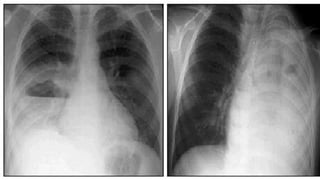

• Chest xray

Interstitial pneumonia